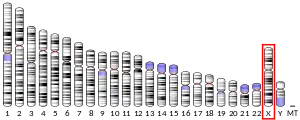

Monoamine oxidase B, also known as MAO-B, is an enzyme that in humans is encoded by the MAOB gene.